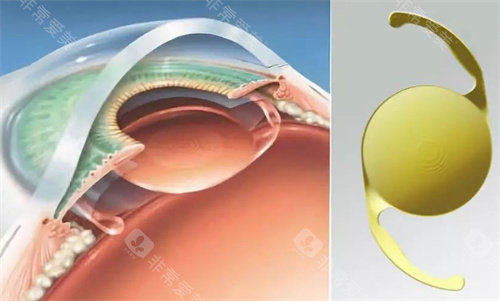

晶体选择是费用差异的核心来源,政策免费提供的为国产基础型单焦点晶体,满足基本视力好转需求。若申请者希望选择功能更优的晶体,需自付差价:

进口单焦点晶体:1400-12000元

高端功能性晶体(如三焦点、景深延长型晶体):15000-30000元起

晶体差价的设定,既确保了基本医疗需求,又为有更高视觉质量追求的患者提供了选择,避免了“一刀切”的僵化模式,兼顾公平与个性化需求。